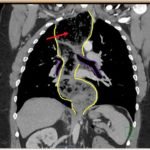

The chest X-ray demonstrated a markedly widened mediastinum (red brackets), raising concern for thoracic aortic aneurysm/aortic dissection, which prompted labs and contrast-enhanced computed tomography (CT) of the chest. The CT revealed a dilated proximal esophagus that narrowed distally (yellow tracing and red arrow), with particulate material, mass-effect on the trachea (purple outline), and bilateral patchy opacities suggesting aspiration. Barium esophagram showed a drastically dilated esophagus filled with contrast (yellow arrow), terminating into the classic “bird’s beak sign” (red arrow) at the lower esophageal sphincter (LES). Esophageal manometry later confirmed achalasia, proving that widened mediastina can have unexpected etiologies.